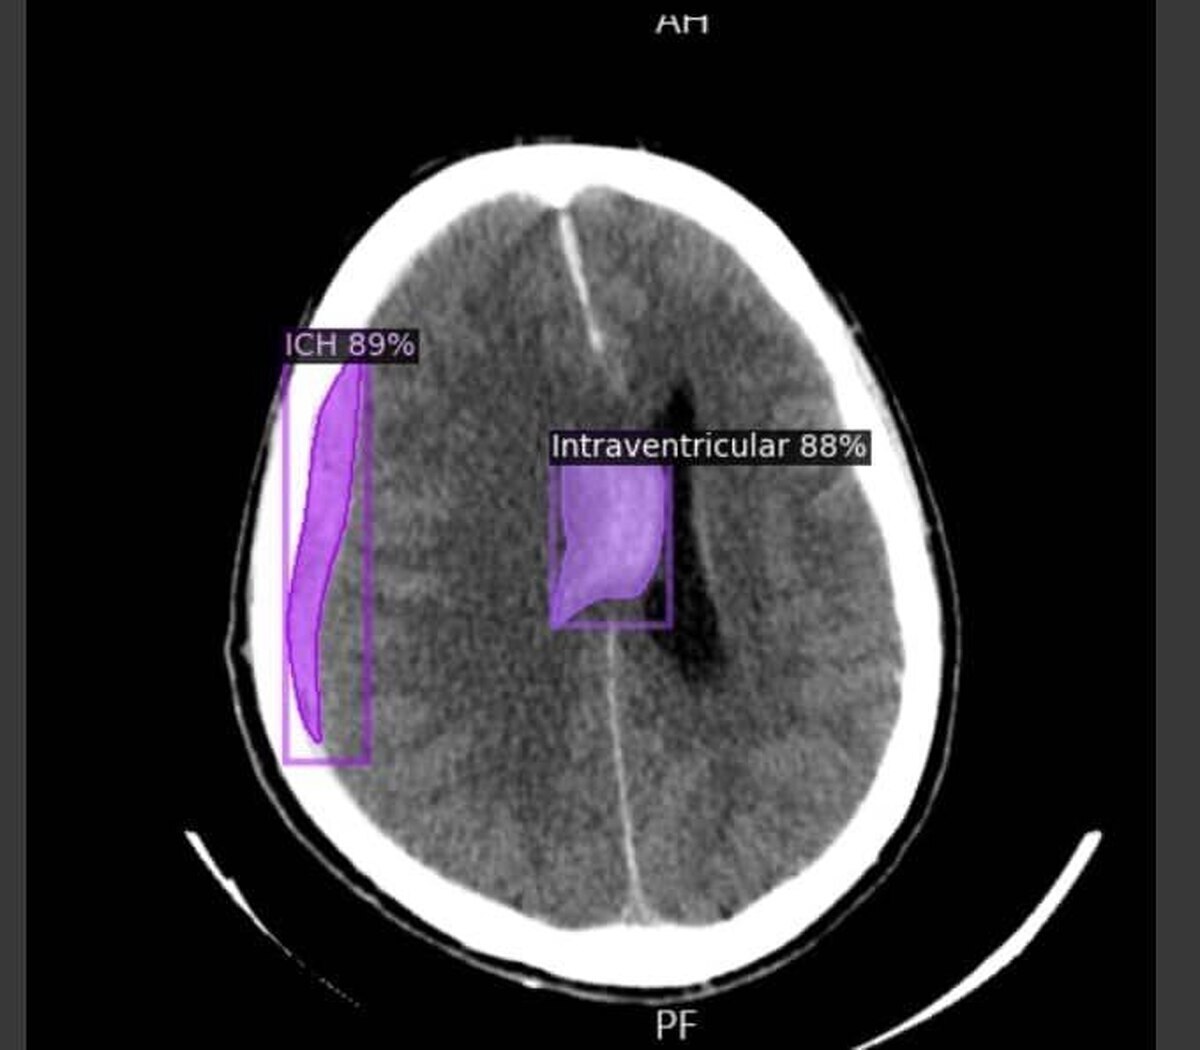

تمكّن باحثون من جامعة كاشان للعلوم الطبية في إيران من تطوير نظام تشخيصي قائم على الذكاء الاصطناعي قادر على كشف النزيف الدماغي وأمراض مثل الزهايمر، الأورام الدماغية، والتصلب المتعدد (MS) من خلال صور الأشعة المقطعية، بسرعة ودقة وتكلفة أقل مقارنة بالطرق التقليدية.

وفي تصريح خاص لوكالة "آنا"، أوضح الدكتور محمد أفشاري، خريج جامعة كاشان وقائد الفريق البحثي، أنّ النظام تم تدريبه باستخدام 30 ألف صورة أشعة مقطعية (ما يعادل بيانات 5 آلاف مريض)، وهو قادر على التمييز بدقة بين الصور السليمة وغير السليمة.

وأشار أفشاري إلى أن الهدف الأولي للمشروع كان تشخيص السكتات الدماغية النزيفية، إلا أنّ النظام يمتلك إمكانات للتوسّع ليشمل أمراضاً أخرى مثل الزهايمر وMS. ومن أبرز مزايا هذا الابتكار تقليص وقت تحليل الصور من قبل الأطباء وتقليل نسبة الأخطاء البشرية.